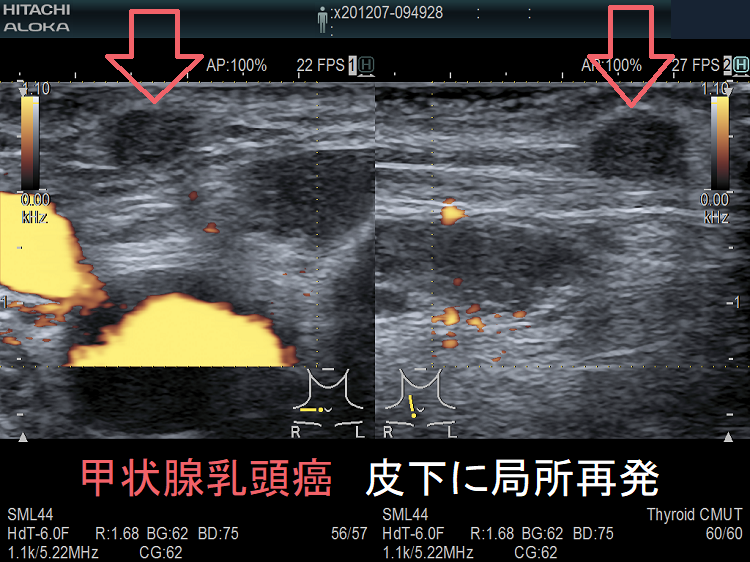

甲状腺乳頭癌 皮下に局所再発 超音波(エコー)画像1

甲状腺乳頭癌 皮下に局所再発 超音波(エコー)画像

甲状腺乳頭癌 皮下に局所再発 超音波(エコー)画像2

甲状腺乳頭癌 皮下に局所再発 (拡大) 超音波(エコー)画像

皮下もしくは前頸筋群内に再発(subcutaneous or intrastrap muscular recurrence)をきたした甲状腺乳頭癌の45%で遠隔転移を認めた報告があります。皮下もしくは前頸筋群内の甲状腺乳頭癌再発では、遠隔転移を伴っている可能性が高い。[J Thyroid Res. 2012;2012:819797.]